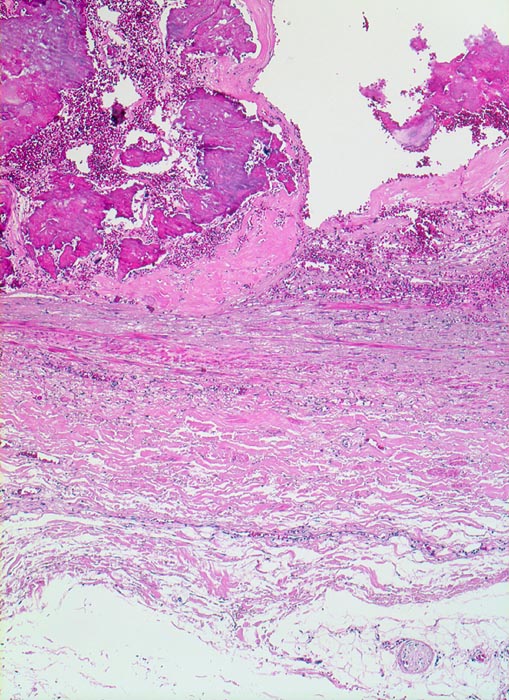

Atherosklerose

Arteria poplitea

Die sklerosierte Intima enthält grobschollige bläuliche Verkalkungen mit frischen Einblutungen. Die Muskelschicht der Media ist atroph.

Patient mit arterieller Hypertonie und 42 Pack Years Nikotinabusus. Klinisch PAVK IIa mit gelegentlichen leichten Schmerzen im rechten Bein nach längeren Gehstrecken.